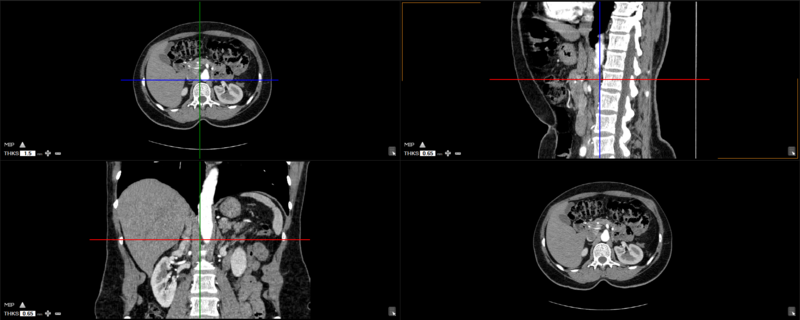

The user can choose from any of these predefined viewing protocols within the MPR mode:

Here are the different viewing protocols you can choose from: